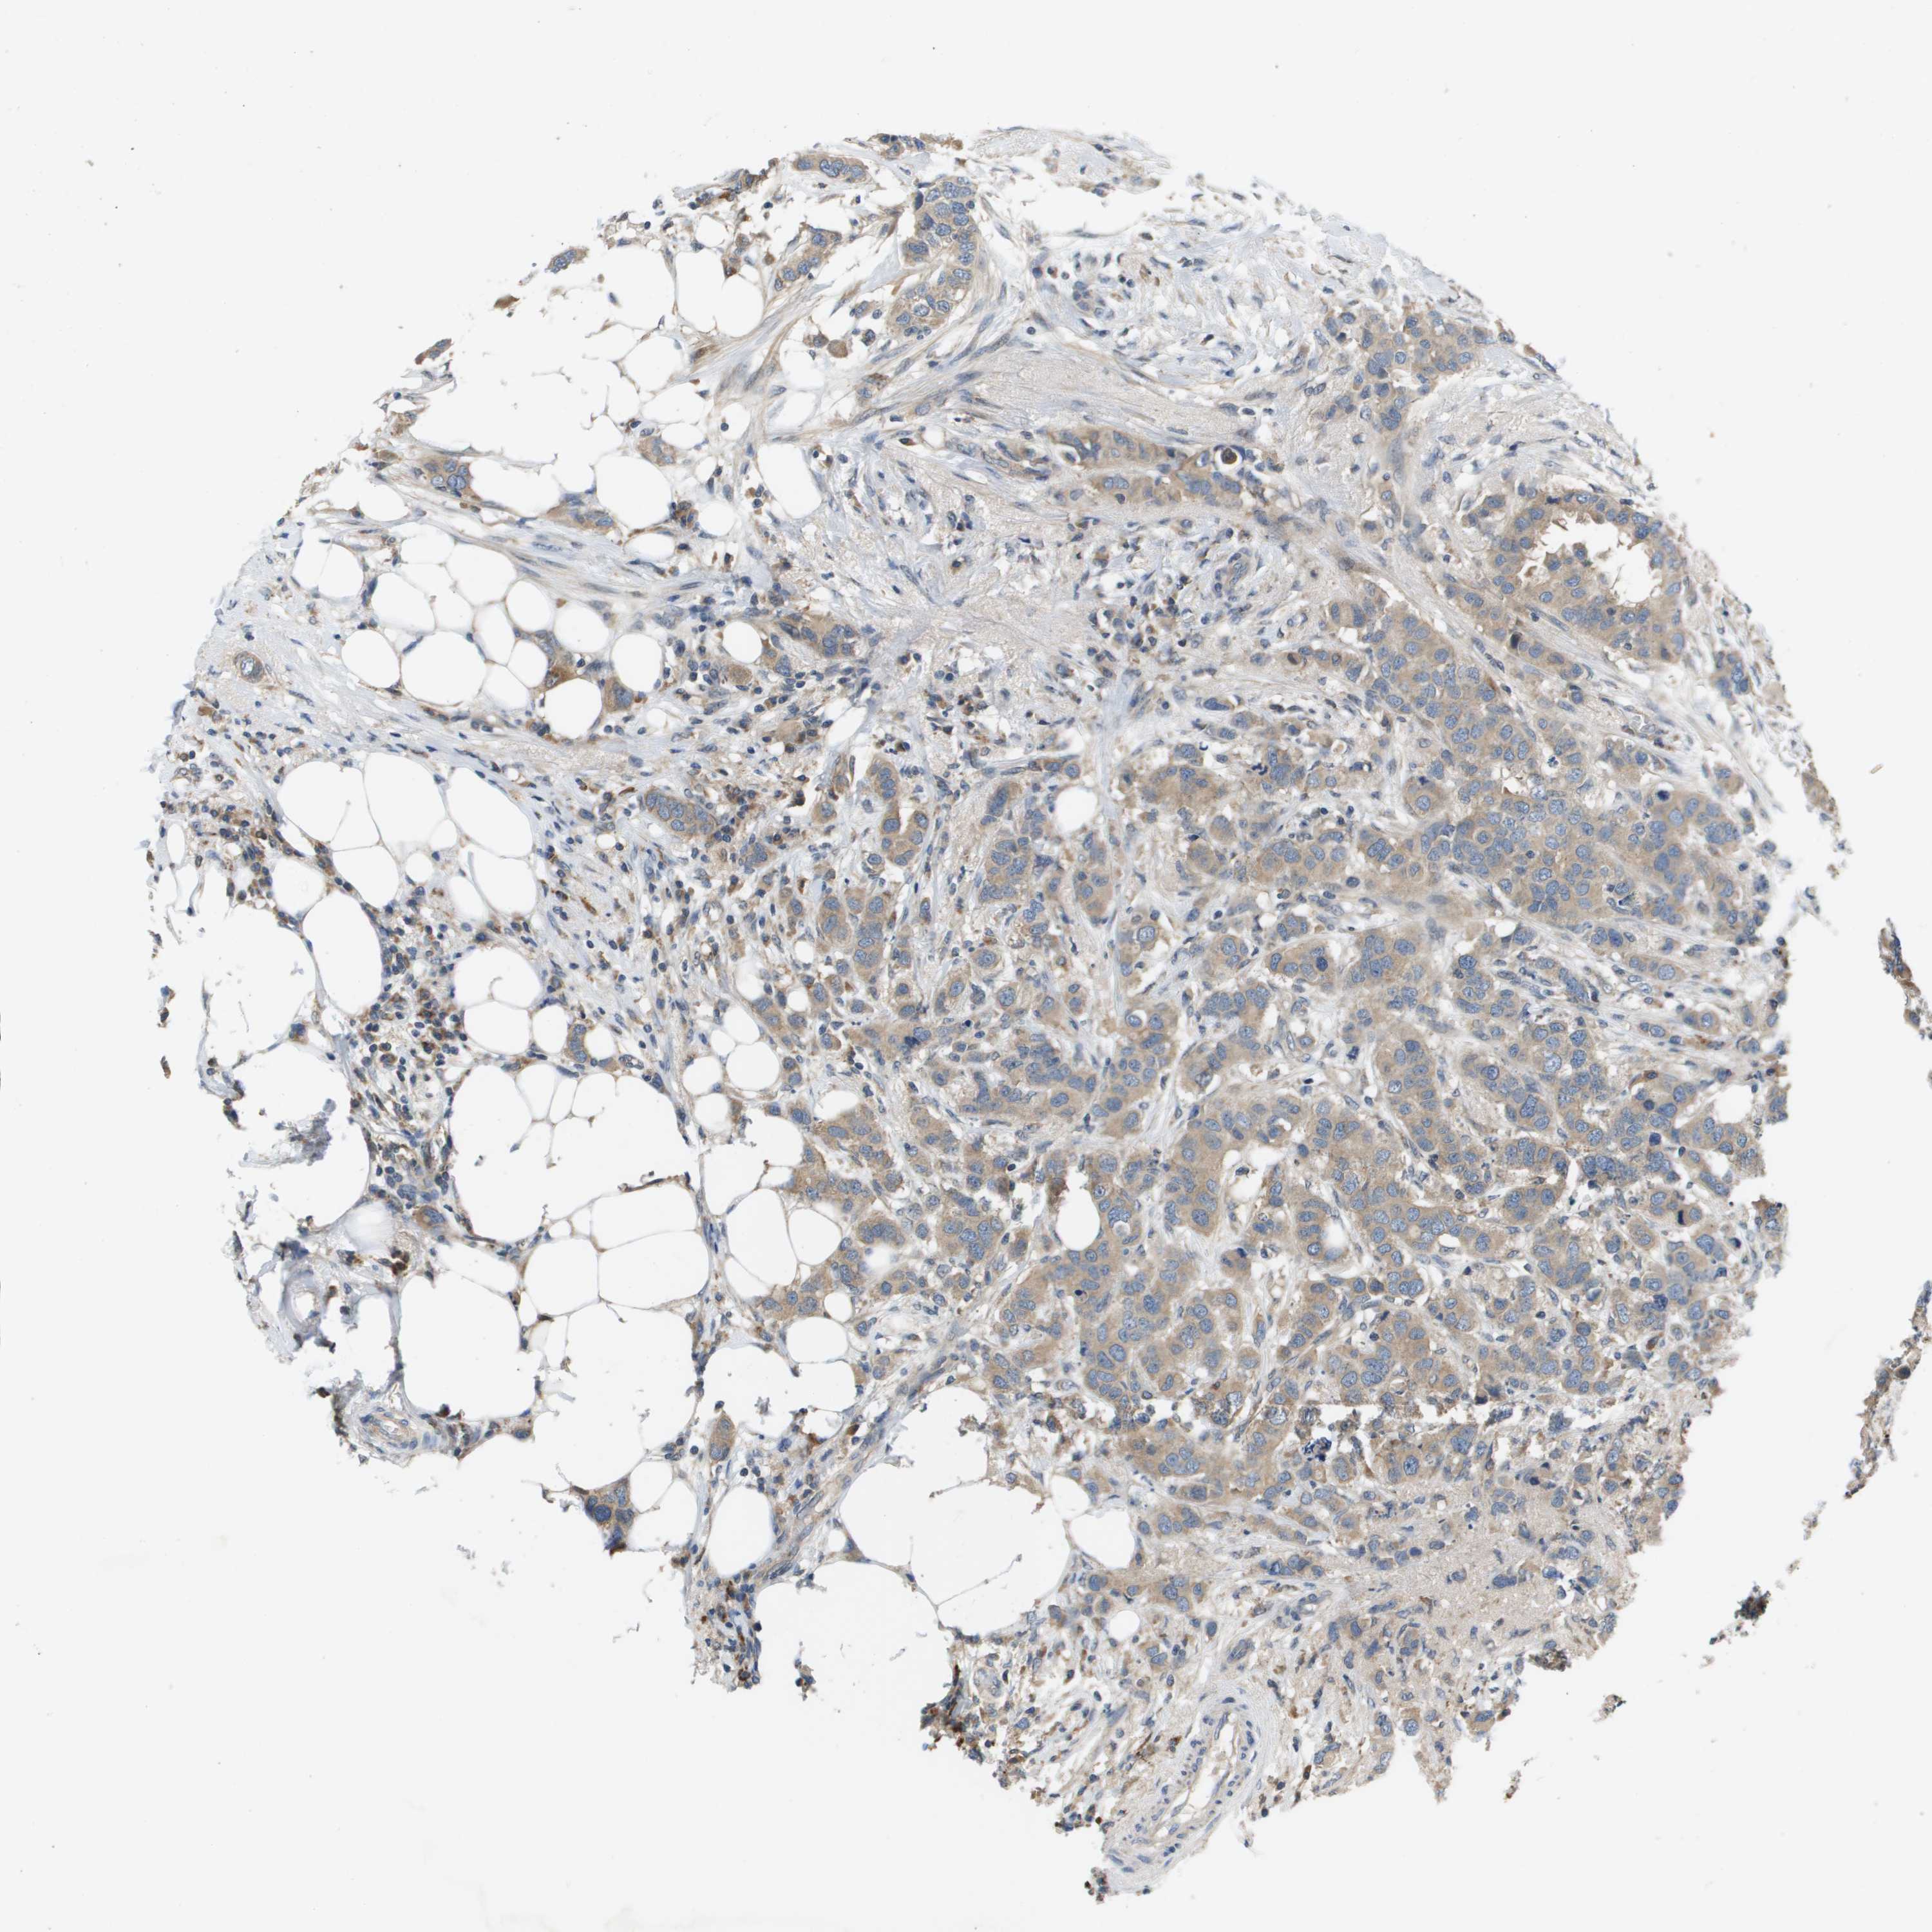

CANCER BREAST CANCER Show tissue menu

BRCA TCGA BRCA VALIDATION PROTEIN EXPRESSION